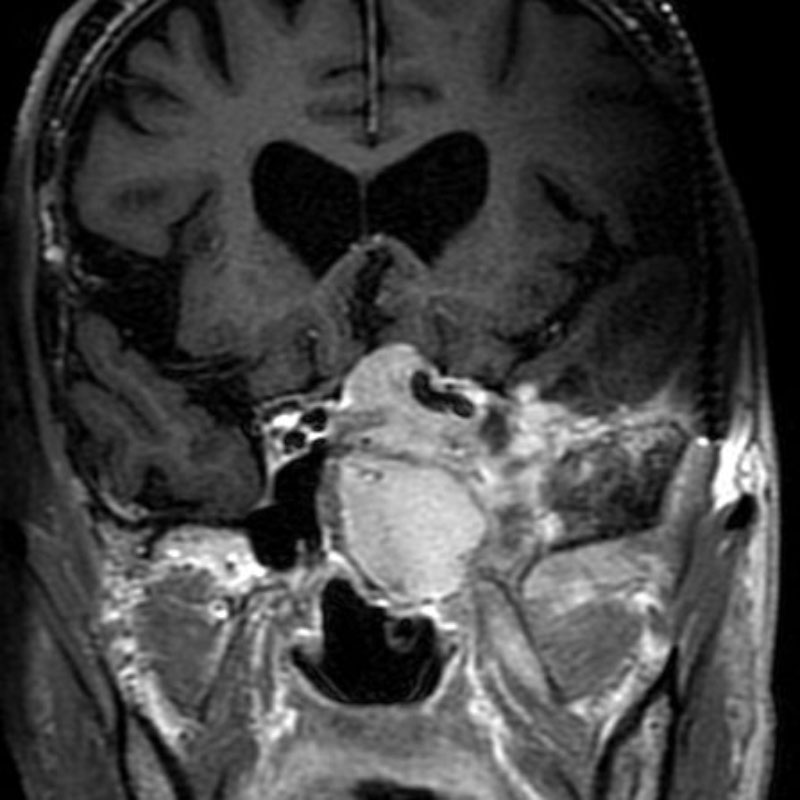

696

'25年11月

70代

眼窩腫瘍

頭蓋内腫瘍摘出術

No.’25_98 手術前1

No.’25_98 手術前2